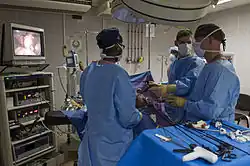

A US Navy general surgeon and an operating room nurse performing a laparoscopic cholecystectomy | |

Laparoscopic cholecystectomy

Laparoscopic cholecystectomy uses several (usually 4) small incisions in the abdomen to allow the insertion of operating ports, small cylindrical tubes approximately 5 to 10 mm in diameter, through which surgical instruments are placed into the abdominal cavity. The laparoscope, an instrument with a video camera and light source at the end, illuminates the abdominal cavity and sends a magnified image from inside the abdomen to a video screen, giving the surgeon a clear view of the organs and tissues. The cystic duct and cystic artery are identified and dissected, then ligated with clips and cut in order to remove the gallbladder. The gallbladder is then removed through one of the ports.[42]

As of 2008, 90% of cholecystectomies in the United States were done laparoscopically.[43] Laparoscopic surgery is thought to have fewer complications, shorter hospital stay, and quicker recovery than open cholecystectomy.[44]